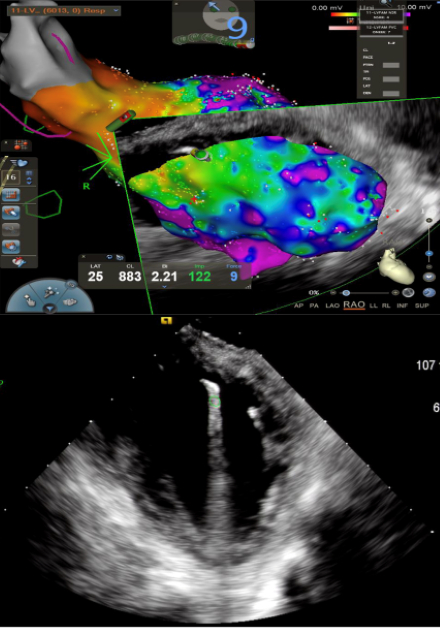

Methods: We retrospectively reviewed patients who underwent EMB from August 2018 to July 2024. EMB was guided by EAM using CARTO system (Biosense Webster, Irvine, CA), and ICE. After accessing the right femoral vein, samples (3-6 per suspected site) were collected using a disposable bioptome and steerable sheath. For left ventricular (LV) biopsies, we used a transseptal approach, and for atrial biopsies, we targeted the atrial septum. In cases of abnormal EAM, multiple samples were taken from the identified areas. When EAM was normal, biopsy targeting was guided by adjunctive imaging. EMB was considered positive if pathology demonstrated findings that directly corroborated the diagnosis.

Results: Of 87 patients who underwent EMB, the median age was 61 years, and 33% were female. EMB sites included the right ventricle (RV) and LV (15/87), RV only (27/87), LV only (38/87), right atrium (RA) and LV (3/87), and RA only (4/87). Pre-procedural imaging was common: cardiac MRI (80%), cardiac PET (65.6%), and/or pyrophosphate scan (8%). Mean LV ejection fraction was 44%, and mean scar burden was 11% on MRI. The overall diagnostic yield was 18%, encompassing a wide spectrum of pathologies (Figure 1A). Positive biopsy results were significantly associated with pre-procedural suspicion of amyloidosis (Odds Ratio {OR} 6.5, 95% CI 1.2-35.5), myocarditis (OR 6.5, 95% CI 1.2-35.5), or cardiac masses (OR 3.9, 95% CI 1.1-13.9), and sampling from both RA and LV (Figure 1B). EAM and ICE during EMB (Figure 1C) were used in 85% and 99% of cases, respectively. No procedural complications were observed.